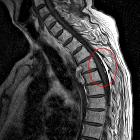

Fett im Subarachnoidalraum

Liquorraum nach Beckenfraktur bei Tarlovzysten: Wohl Fettembolie vom Becken bis kranial. Fallbericht hier

- Fett im Subarachnoidalraum bei Beckenfraktur

- fat in subarachnoid space after spinal fracture